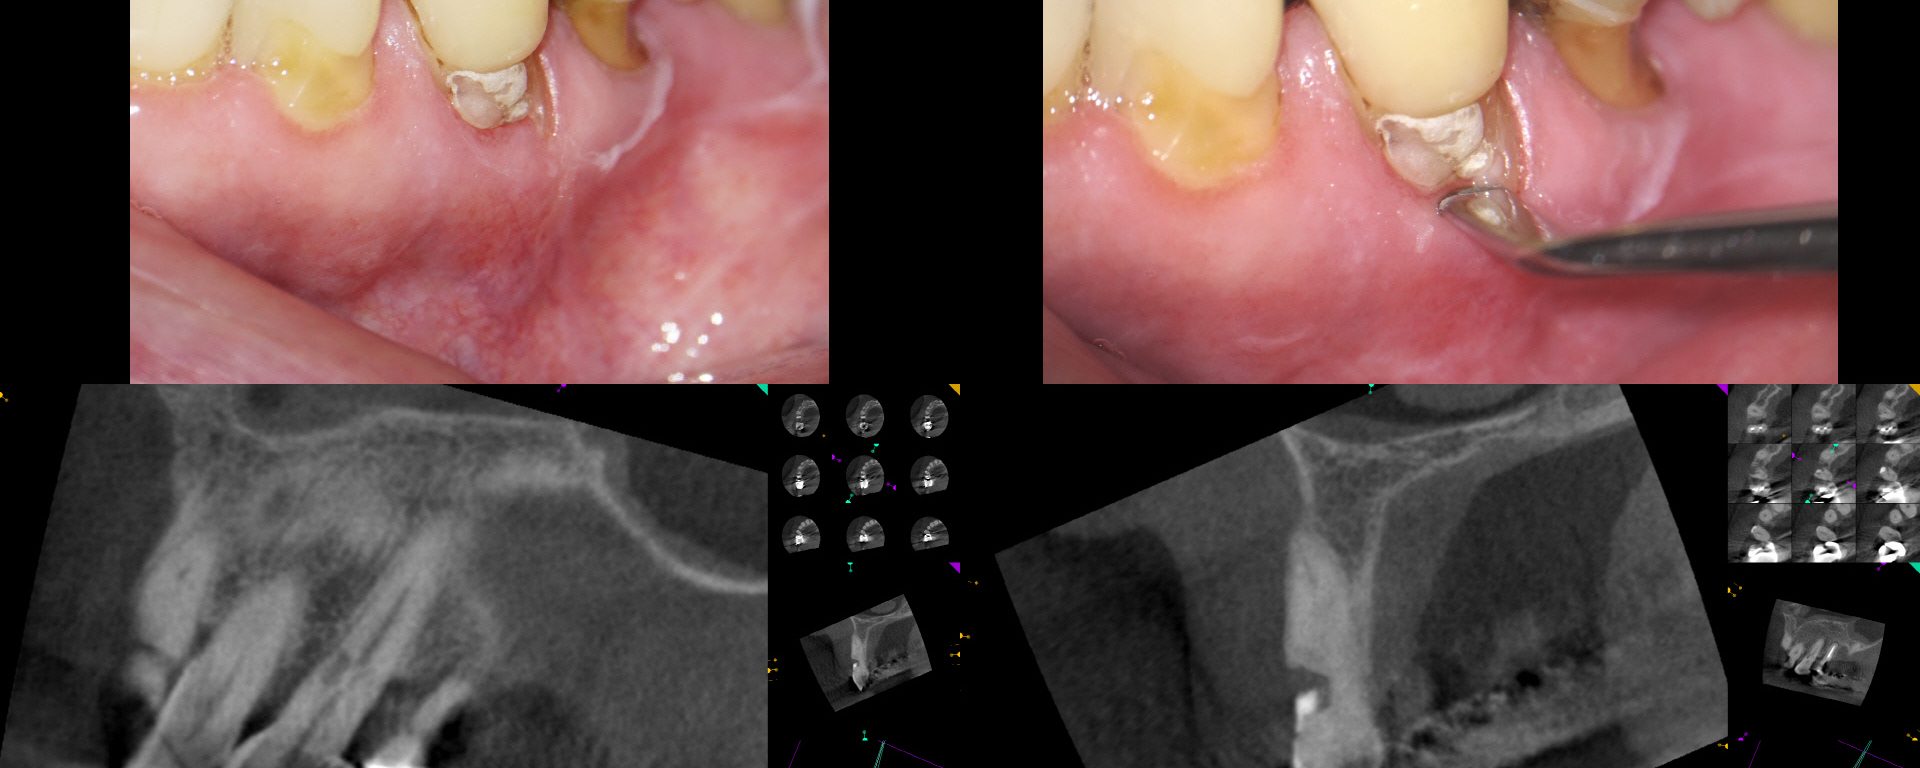

External Cervical Resorption

September 7, 2018 3 comments